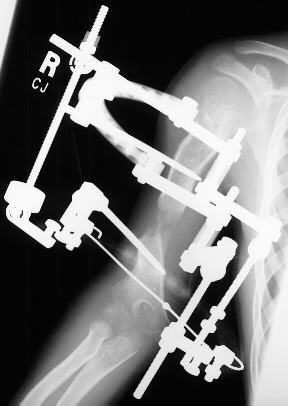

At the age of 11 years 6 months the patient underwent corticotomy, application of Ilizarov's external fixator and angular correction of right humerus. A 5 mm EBI half-pin was placed in the proximal humerus laterally. Lateral incision was placed over the distal humerus to identify the radial nerve; a small incision was placed through the brachialis muscle down to the humerus at the apex of the deformity for corticotomy. A significant amount of malrotation, approximately 100 of the 150 degrees malrotation, was corrected by internally rotating the distal fragment. A 1.8 mm Olive wire was drilled medial -to-lateral across the distal fragment just above the olecranon fossa. The frame was modified for 5/8`` ring with the open aspect anteriorly. It was placed across the Olive wire and the arch was placed posterolaterally. The angular correction devices were placed medially, and the lengthener was placed laterally. An additional 5 mm half - pin was placed posteriorly to the transfixion pin distally through the distal humerus.

Lengthening started 7 days after the corticotomy with rate of 1 mm / day. Nine weeks after the corticotomy there was good bone healing with 4 cm gap of new bone. A 30 degree of flexion contracture of the right elbow developed. Hardware was removed and good new bone was noted .